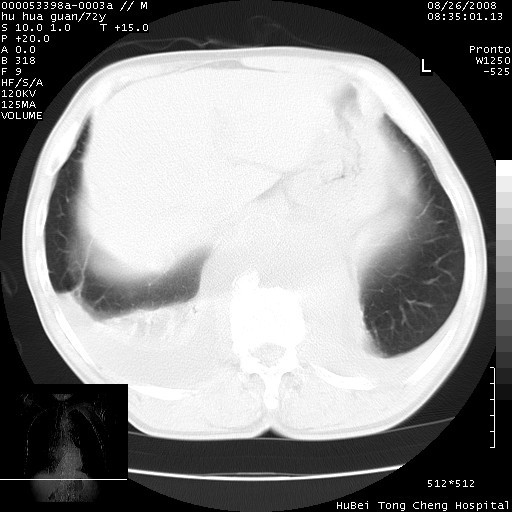

标题: CT15582:M,72Y。请老师帮分析胸部病变。

胸腔b超:胸腔积液。胸膜腔抽水化检:l 81%。

可以明确的说。肯定不是主动脉夹层破裂出血!考虑为淋巴瘤或间叶组织来源的恶性肿瘤可能性大。右肺小结节建议薄层观察,如能发现恶性征象,那椎前改变就考虑为转移所致。至于双侧少量胸水乃静脉血回流受阻所致。

图像及窗宽窗位均不理想。周围性肺癌/胸腔积液/纵隔积液。

1、右肺周围性肺癌、胸腔积液(双)

2、建议食道吞钡和增强检查排除食道和主动脉病变

3、后纵隔淋巴类肿瘤

1、右上肺结节病变,肺泡癌不除外,请随诊;左下肺近后纵隔病变,考虑纵隔型肺癌侵犯大血管可能;

2、右下肺背段少许炎症,双侧胸腔积液,右下肺纤维索条。

降主动脉前移位,后纵隔占位

后纵隔占位,降主动脉前移位;双侧胸腔积液;应排外食管病变侵犯血管可能;

建议排除结核引起的冷脓肿。